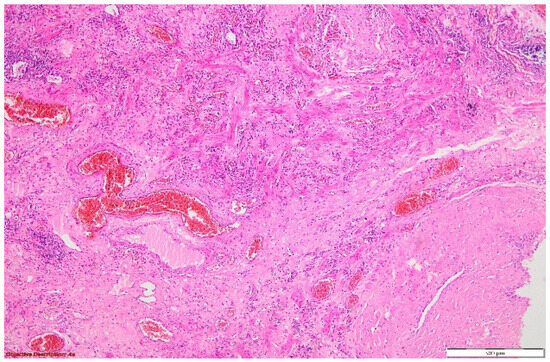

Figure 7. Pulmonary tissue with an enlarged bronchiolar lumen (bronchiectasis →), containing mucus and rare inflammatory elements; smooth muscle hyperplasia of the arterial media, and important polymorphous inflammatory infiltrate (predominantly lymphocytic) in the peri-bronchiolectatic interstitial parenchyma. HE, 40×.